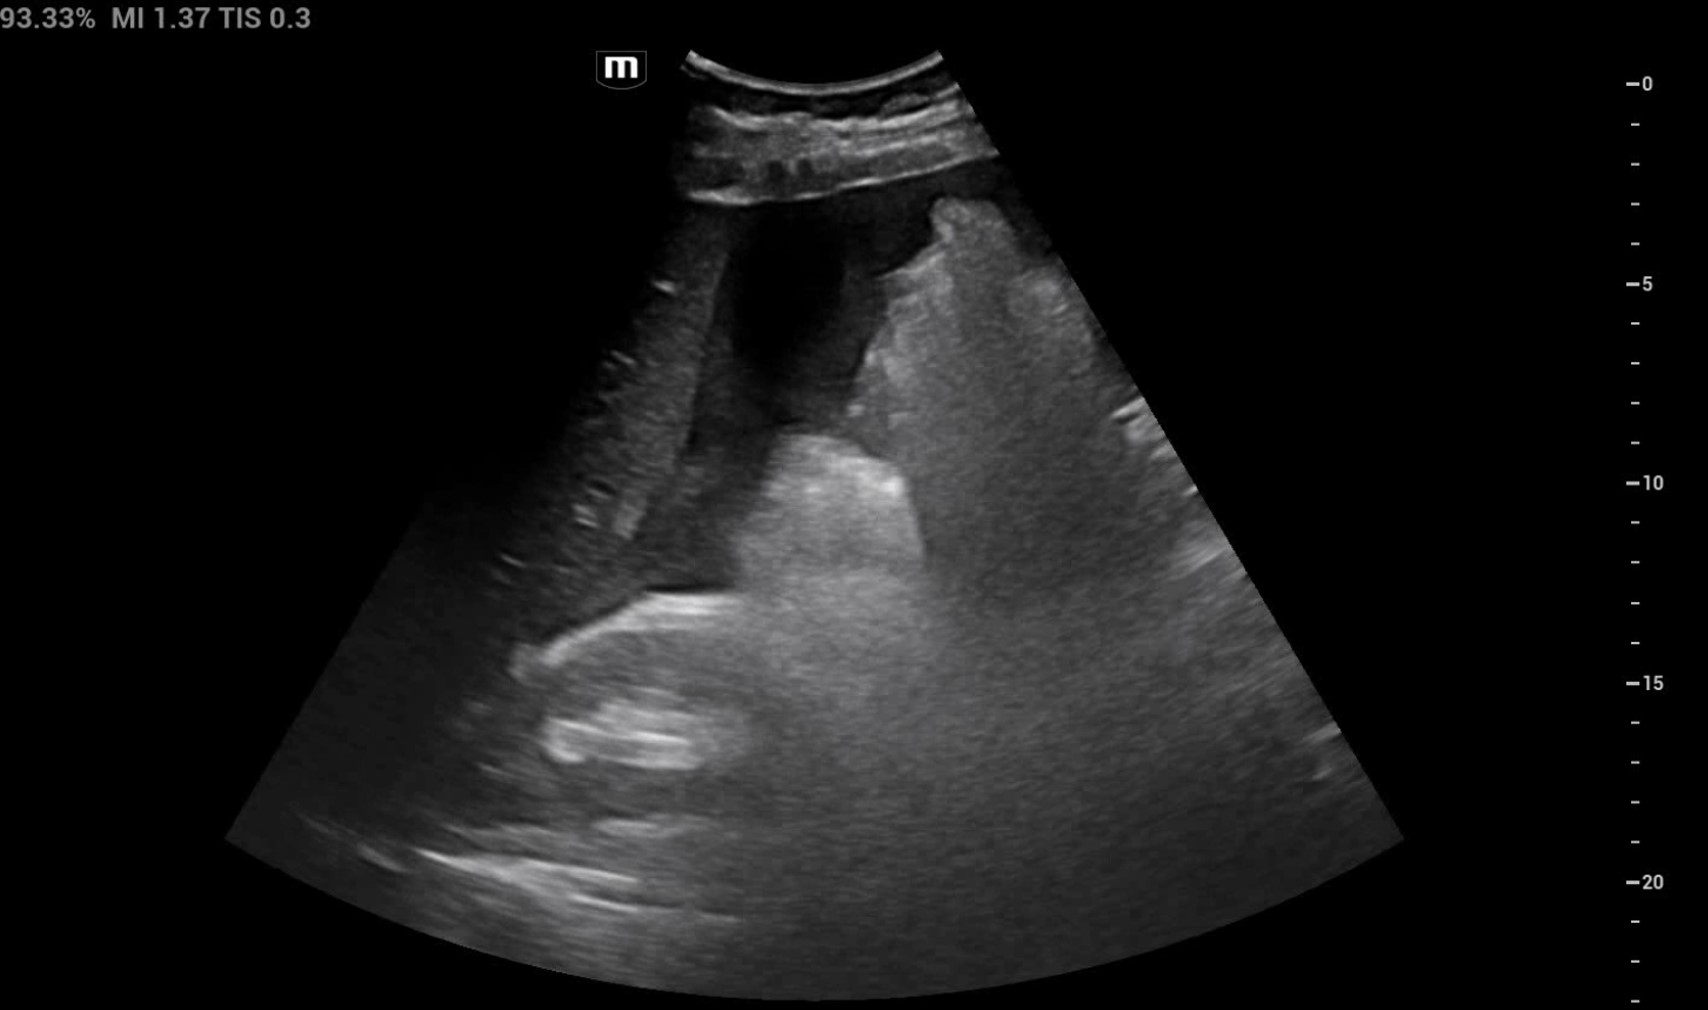

Se realiza ecografía clínica con esplenomegalia de 18 cm con líquido libre en receso esplenorrenal e interasas. Hígado con tamaño y morfología normal con atenuación aumentada de parénquima en probable contexto de hepatopatía difusa. Riñones de tamaño y morfología normal, con buena diferenciación corticomedular. No se observa dilatación de la vía excretora. Vejiga escasamente replecionada sin visualizar engrosamientos focales de la pared.

En base a estos hallazgos se realizó TAC (tomografía axial computerizada) de abdomen donde se confirmaron los signos de hepatopatía con hipertensión portal. Esplenomegalia y rotura contenida de bazo sin signos de hemorragia activa en el momento actual.